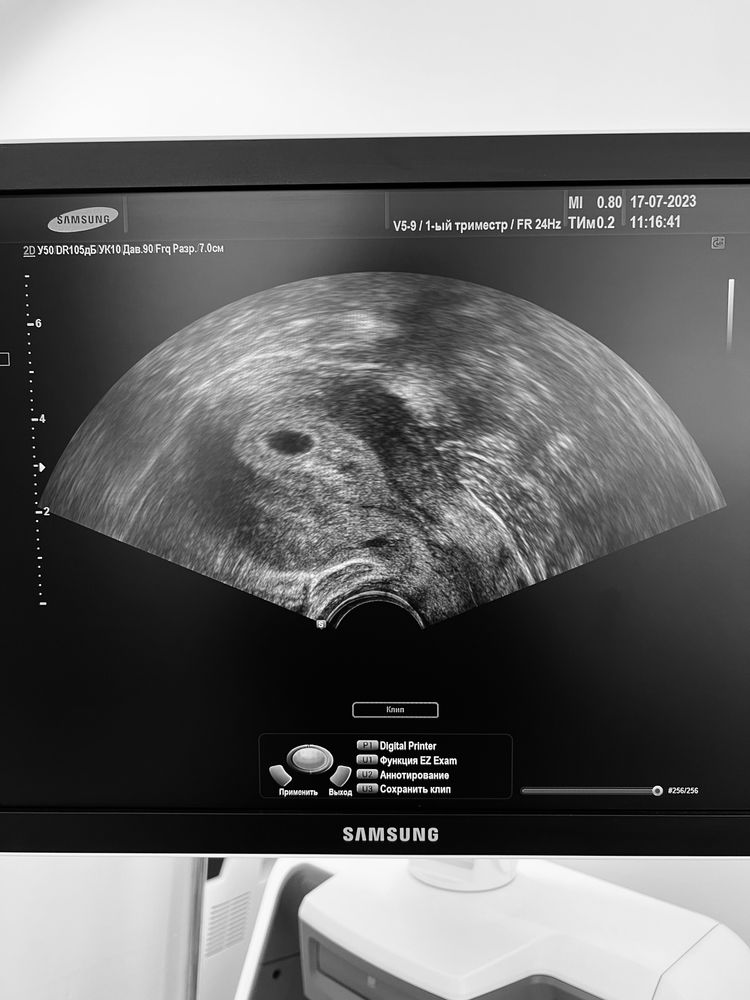

17.07.2023г было УЗИ на 21дпп

ПЯ -8 мм, ЖМ есть сказали, все хорошо, повторить узи через 11 дней.

подскажите не вижу ЖМ переживаю по поводу размера, хочу услышать слова поддержки.

У вас жм там виднеется справа))не переживайте все хорошо, через 11 дней и сб послушаете, я на 19 дпп делала узи было только пя 6мм жм даже не замерил узист и фото с монитора что я сама сделала жм вообще не было видно (сама пошла на это узи не к своему ре) на 25дпп уже свд 11 ктр 3 и пульсацию показали

Мне кажется видно жм в уголочке. Да и если врач сказал, значит все есть, не волнуйтесь